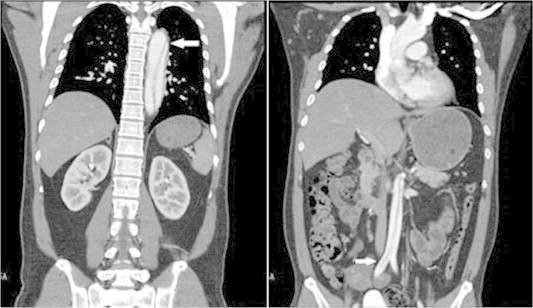

+0+ 阳光融和医院成功救治一例A型主动脉夹层患者其特点是主动脉内膜撕裂后,血液进入主动脉壁内形成夹层,随时可能引发主动脉破裂、心包填塞、急性心肌梗死等致命并发症。 更严峻的是,检查结果显示主动脉夹层累及:主动脉根部、升主动脉、降主动脉至双侧髂血管,右冠状动脉开口、头臂干、左锁骨下动脉、腹腔干等形成夹层及壁...

警惕!主动脉夹层:胸背痛背后的隐秘致命威胁其中最需要警惕的就是主动脉夹层。这是一种与时间赛跑的紧急情况,往往是高血压患者的无声杀手。 什么是主动脉夹层? 主动脉是人体的主要供血通道,负责将心脏泵出的血液输送到全身。当主动脉内膜因某些原因破裂时,血液会进入血管壁中层形成所谓的“真假腔”。随着病情发展,...

≥ω≤ 主动脉夹层:隐藏在胸背痛背后的致命杀手就是主动脉夹层。这种“时间就是生命”的急症,常常是高血压患者的无声杀手。 什么是主动脉夹层? 主动脉是人体的“主供血管道”,负责将心脏泵出的血液输送到全身。而主动脉夹层指的是,主动脉内膜因某些原因破裂,血液进入血管壁的中层,形成“真假腔...

主动脉夹层近期高发!西安一医院两天收治14人!其中12例A型主动脉夹层,2例B型主动脉夹层。患者年龄最大的72岁,所有患者都得到了及时有效的救治。西安交大一附院心血管外科副主任李勇新:“主动脉是从心脏延伸出来的一根给全身供血的大动脉,由内膜、中膜和外膜三层组成,由于高血压等原因导致主动脉内膜受损,当主动脉内膜...